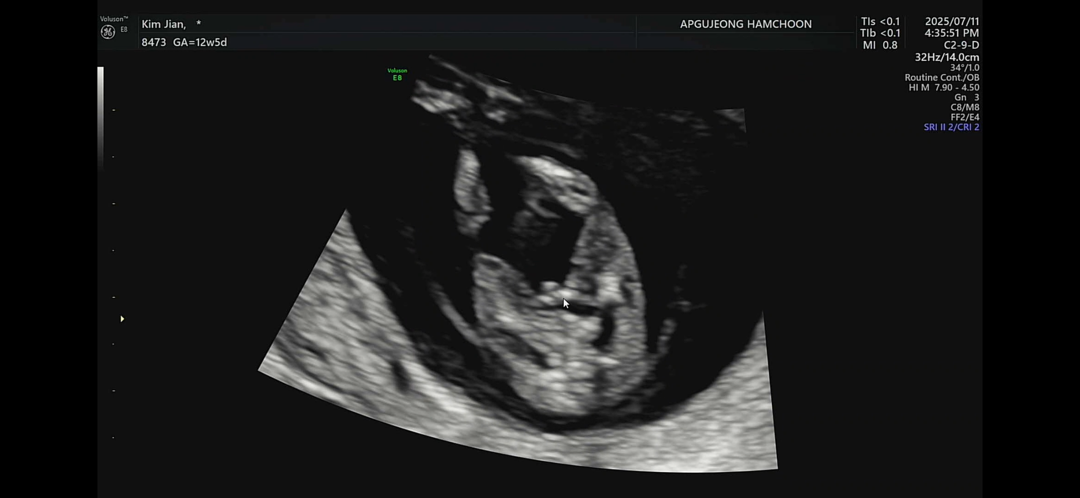

혹시 남아로 보이세요? 여아로 보이세요? 저번에 올렸을때 여아 같다고 하셨는데.. 반전된 걸까요?? 아빠랑 목욕탕 가야한다고 하셔서...

마우스가 가리키는 곳이 삼각점 같은데욧?! 아들같아용~